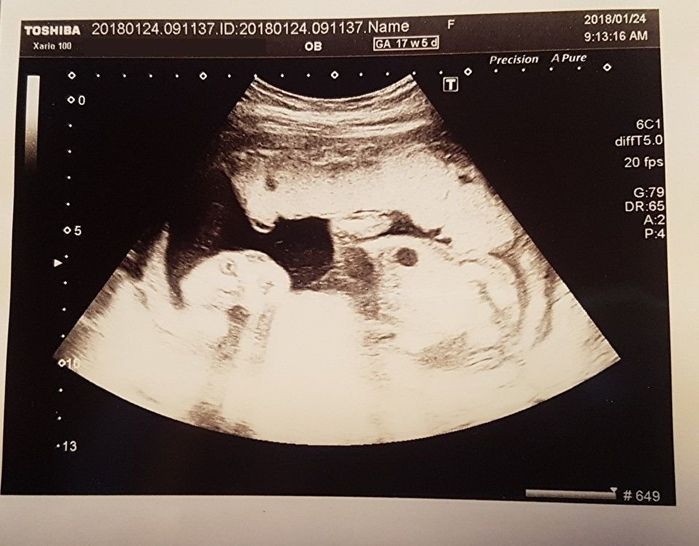

妊娠17週目 カメラ目線でナイスショット!

この日は超音波技師さんに、エコー写真を撮ってもらいました。特別な日とわかるのか、しっかりカメラ目線。左に顔、目と鼻、口と耳が形になっているのがわかります。クリクリの目がこっちを見ていて、狙ってポーズをとっているのかな?

性別を聞いてみると「おそらく女の子でしょう」とのこと。つわりは落ち着いてきたので、無理のない範囲で歩くことを心がけ始めました。